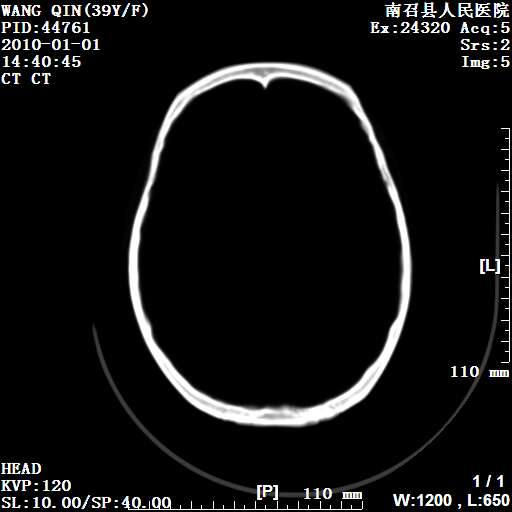

以下是引用随光逐影在2010-1-22 9:03:00的发言:[br]考虑左侧中颅窝(蝶骨翼区)脑膜瘤侵犯蝶骨翼并突入左侧眼眶。

以下是引用水过无痕在2010-1-22 14:55:00的发言:[br]一、定位:颅外占位;二、定性:恶性可能性大;三、组织来源:来源于左侧眼外直肌或其他部位;考虑为:横纹肌肉瘤>转移瘤>脑膜瘤.